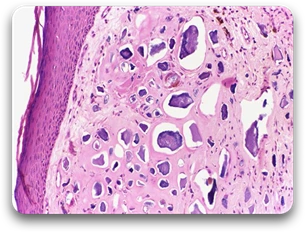

Morphology

- Gross examination: Calcium salts are seen as fine white granules or clumps, often felt as gritty deposits.

- Histologic examination: Appear as intracellular and/or extracellular basophilic deposits, and with time, there may be formation of heterotopic bone in foci of calcification.